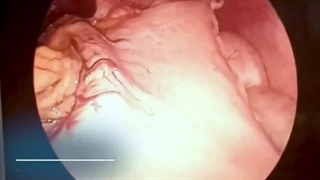

پخش صدا راهکار کاهش آمبولی بعد از عمل چاقی اشتراکگذاری لیست پخش ۰ نظر ۰ نظر دانلود دانلود ویدیو دانلود کیفیت 720p ۱۲.۰۴ مگابایت دانلود کیفیت 480p ۷.۷۵ مگابایت دانلود کیفیت 360p ۵.۵۸ مگابایت دانلود کیفیت 240p ۳.۶۹ مگابایت دانلود کیفیت 144p ۲.۵۱ مگابایت گزارش تخلف بیشتر گزینههای بیشتر لیست پخش لایکها گزارش تخلف ۰ لایک دکتر سید علیرضا آذرپیکان منتشر شده در تاریخ ۱۴۰۱/۰۵/۰۲ این کانال دنبال شد دنبال کردهاید دنبال کردن این کانال دنبال کردن برای اطلاعات بیشتر نام دکتر علیرضا آذرپیکان را در گوگل سرچ کنید و وارد سایت drazarpeikan شوید. ادامه نظرات لبخند لبخند لغو ثبت نظری برای نمایش وجود ندارد.